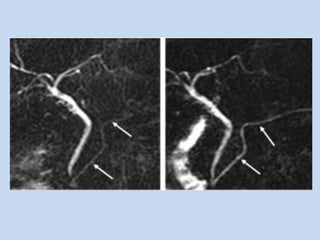

• In pancreatitis :

- especially when ERCP is contraindicated in ongoing

acute pancreatitis.

- in detecting common ductal manifestations of chronic

pancreatitis such as dilatation, strictures, stones &

thoracopancreatic fistulas.

• In pancreatic carcinoma :

- depicts the ducts obstructed by the pancreatic

mass & localizes the obstruction to pancreas.

- “double duct sign” is observed in case of

pancreatic head mass. ( non- specific as it may

seen in chronic pancreatitis)

- MRA done in conjunction – assesses the

resectability..